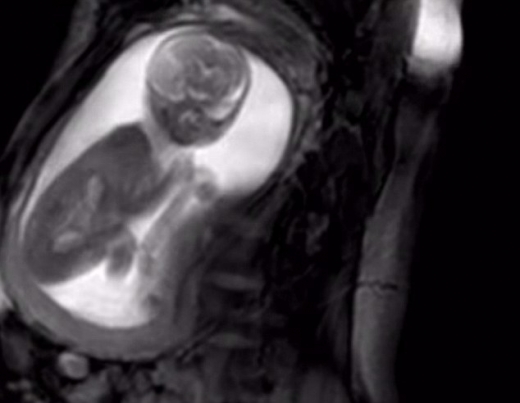

영국 정부가 1000만 파운드(약 143억 원)를 투입해 추진 중인 의료 프로젝트 ‘아이 파인드’(iFIND)의 첫 번째 성과가 공개됐다.

그 성과는 새롭게 개발한 고성능 자기공명영상(MRI) 검사로 파악한 태아의 영상이다.

24초 분량의 이 영상에는 임신 20주차 어머니의 배 속에 있는 태아가 기존에 없던 선명한 모습으로 비춰지고 있다.

MRI 영상만으로 아기가 고개를 돌리거나 탯줄을 손으로 잡고 또는 다리를 걷어차는 등의 모습을 명확하게 볼 수 있다.

이는 지금까지의 MRI로는 불가능한 것이라고 한다.

‘아이 파인드’에 참여한 데이비드 로이드 킹스칼리지런던 교수는 “임신 20주차의 태아를 선명하게 촬영하는 것은 어려운 일”이라고 말했다.

왜냐하면 이 시기의 태아는 키가 고작 20㎝ 정도에 불과하기 때문. 몸집이 너무 작아 일반적인 MRI로는 선명하게 볼 수 없다는 것이다.

로이드 교수는 “새롭게 개발한 MRI는 주파수의 매우 짧은 파장을 이용해 그것을 가능하게 하고 있다”고 말했다.